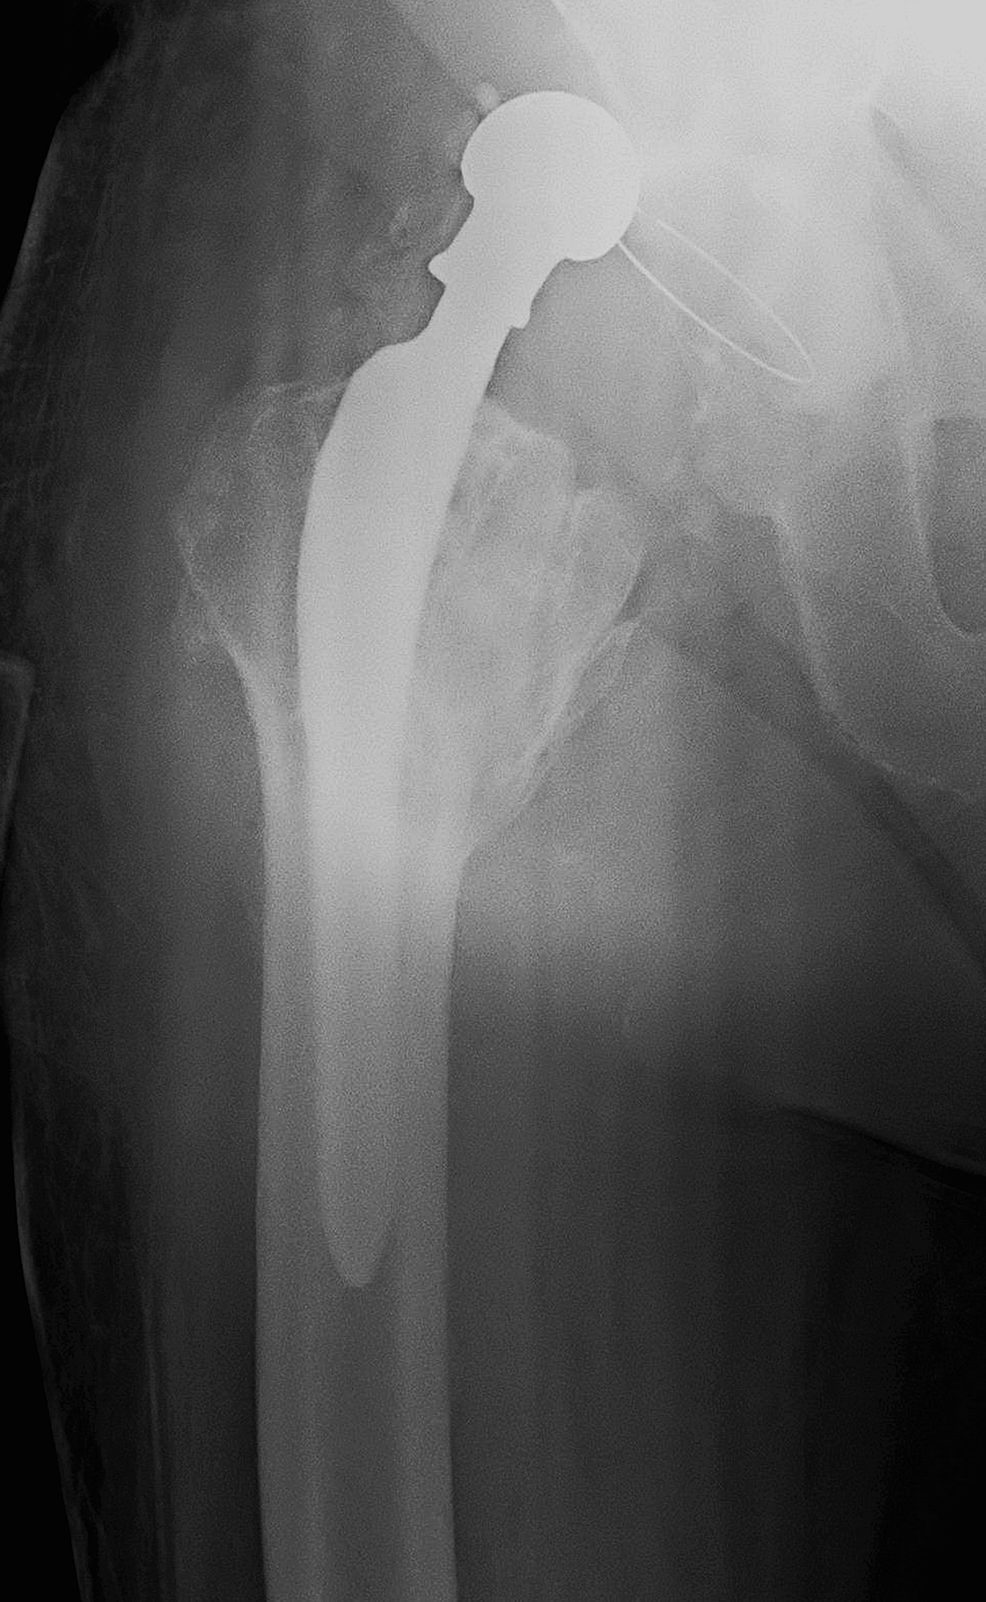

A magnified view of the dislocated right Exeter total hip replacement Total Hip Replacement Dislocation Treatment After a total hip replacement, you will be able to resume most activities. One third of cases will require surgical treatment (e.g., revision. But if you have a replacement hip, it may have dislocated more easily, from something as simple as sitting on a low chair or crossing. Treatment is closed reduction of the hip. Treatment is closed reduction of. Total Hip Replacement Dislocation Treatment.